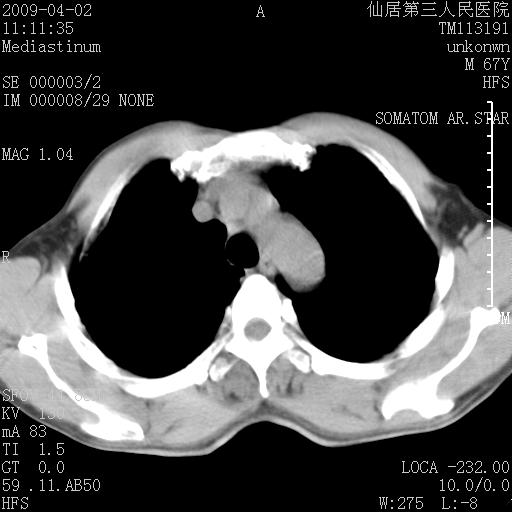

患者老年男性,乏力畏寒来诊,摄胸片示右下肺感染性病变,抗炎两周后复查胸片,无好转有进展。

后做ct平扫表现如下:

病灶呈蜂窝征,纵隔多个淋巴结肿大;肺泡癌需考虑

我认为普通的感染应该可以除外,间质性肺炎可能性较大,但如何解释纵膈的淋巴结肿大呢

考虑双肺间质性改变(间质纤维化?)伴右肺下叶感染。

支持11楼,考虑肺结核.年䶨;大,抗炎无效.纵隔淋巴结肿大.老年人下肺结核要警提